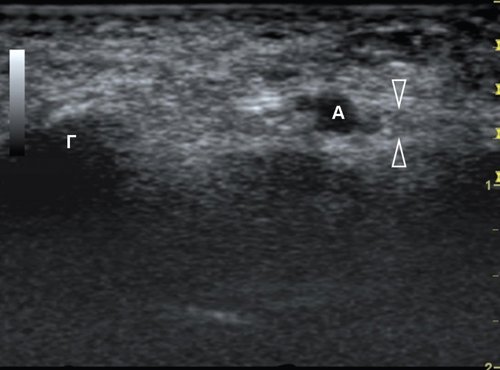

Рис. 17. Панорамная сонограмма продольного среза глубокого и поверхностного сухожилий сгибателя на уровне пальца позволяет визуализировать места их прикреплений к фалангам и четыре блока (А). Лучше всего доступен визуализации блок А2 (стрелка).